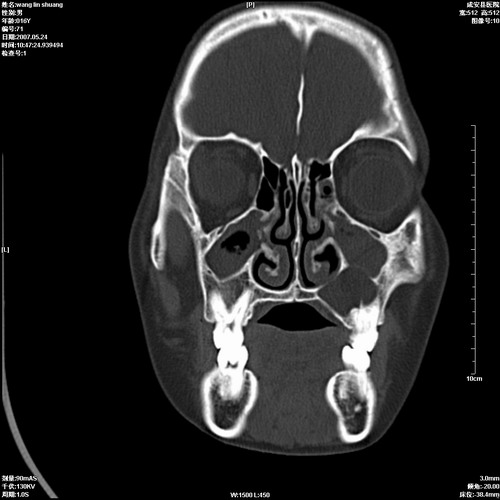

病人,男 16岁,鼻旁右肿胀,其余无不适感,ct图片

1、典型右侧根尖囊肿。

2、双侧上颌窦、筛窦、蝶窦炎

1\\左侧上颌骨含牙囊肿

2\\两上颌窦炎

右侧上颌骨含牙囊肿.双侧上颌窦炎症.

右侧上颌骨含牙囊肿.双侧上颌窦、蝶窦右侧炎症.

1、左侧上颌骨含牙囊肿。